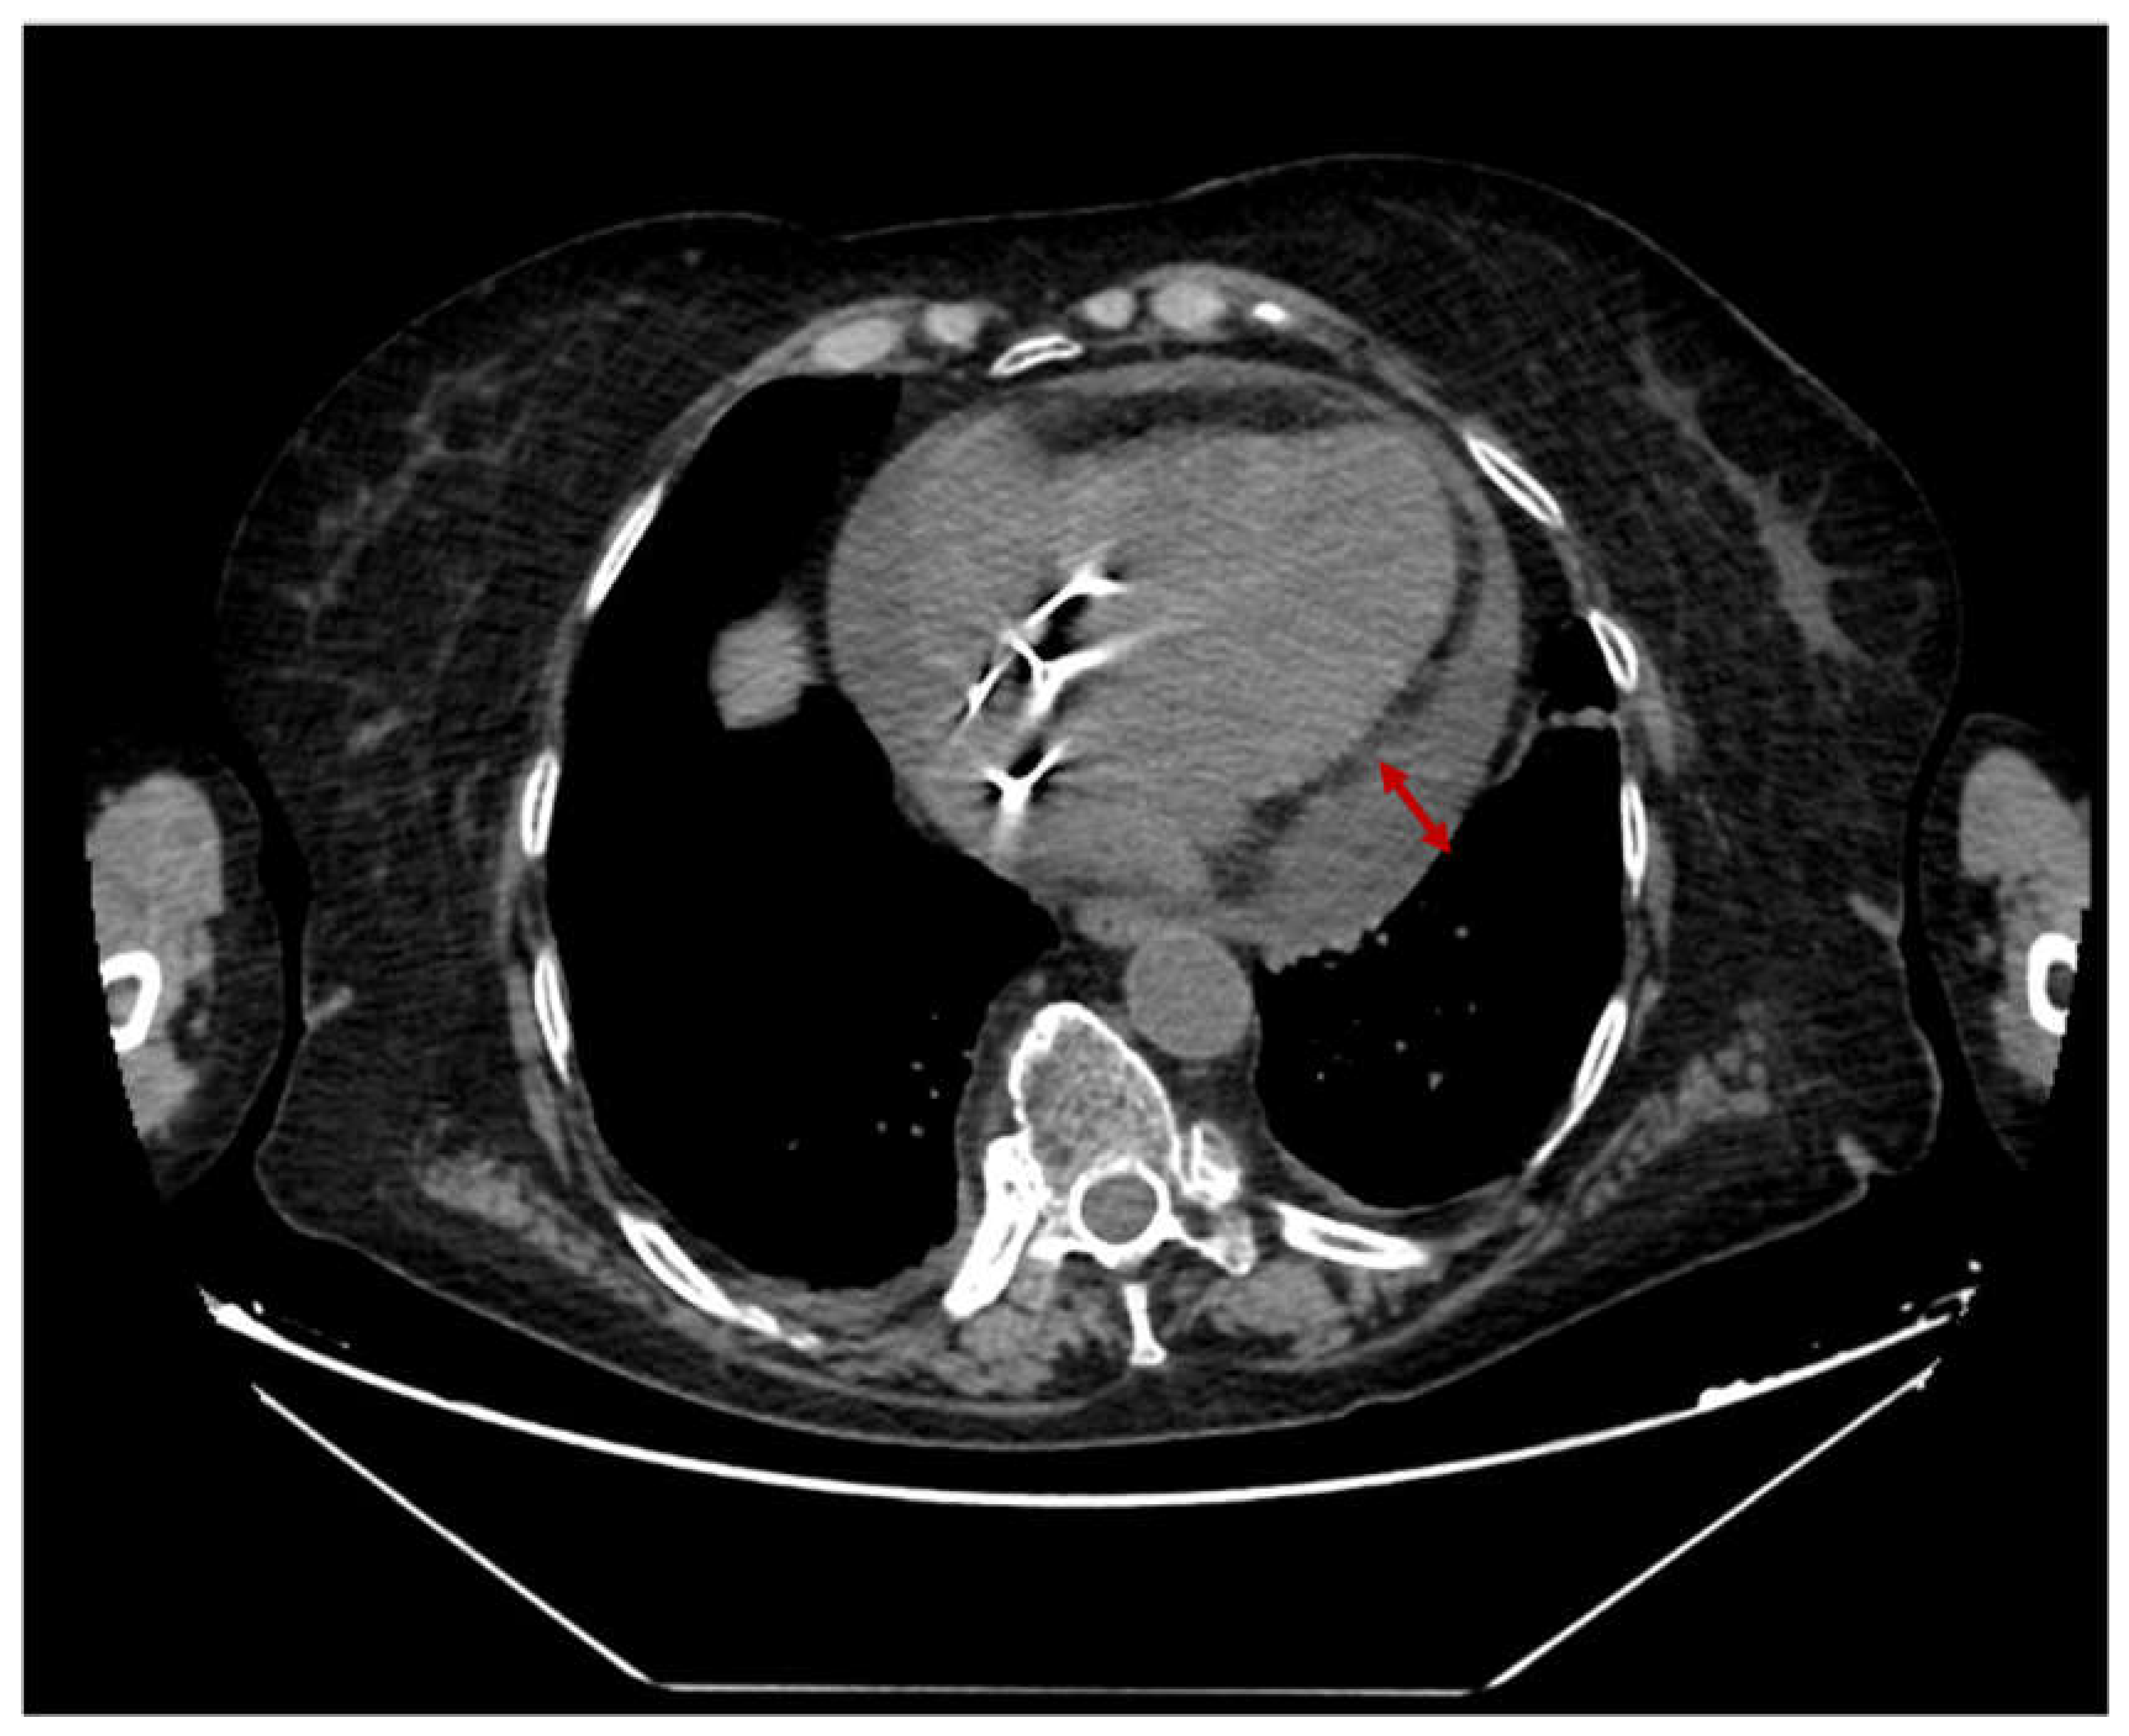

2.4. Case 4